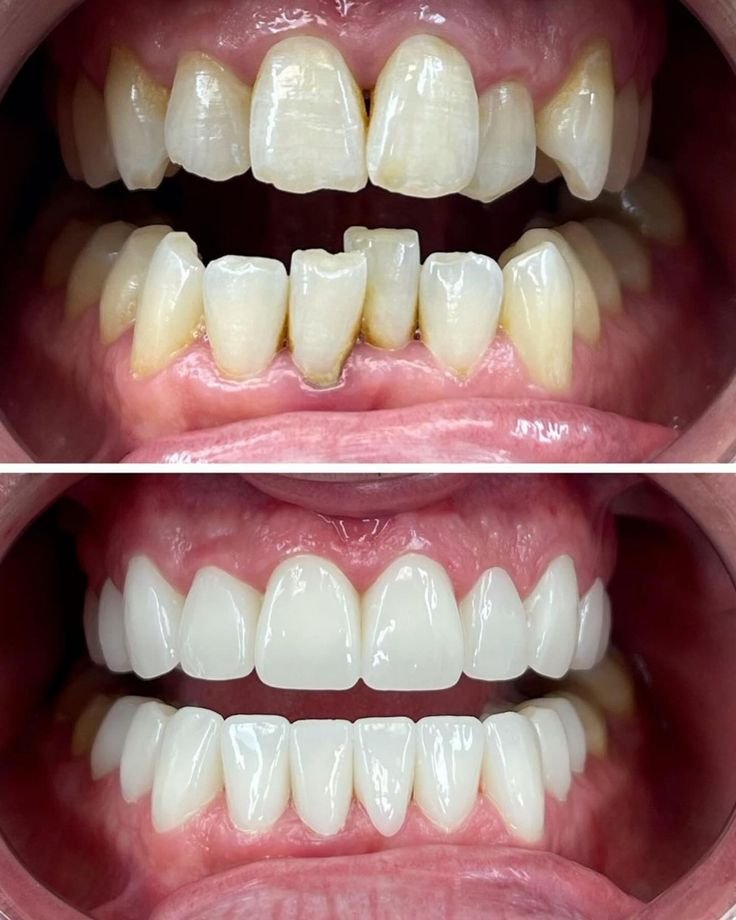

Fixed teeth refer to a range of dental treatments designed to permanently replace missing or severely damaged teeth. Unlike removable options like dentures, fixed solutions are securely anchored in your mouth, offering a level of stability and comfort that is very similar to natural teeth.

These permanent restorations allow you to eat, speak, and smile with complete confidence, without the worry of slippage or discomfort. They are the premier choice for restoring both function and aesthetics to your smile.

We offer several excellent options for permanent tooth restoration. Dental Implants are the gold standard, replacing the entire tooth from root to crown for unmatched stability. Dental Bridges are used to "bridge" a gap by anchoring a replacement tooth to the adjacent natural teeth. Dental Crowns are placed over a single damaged or weakened tooth to restore its strength and appearance.